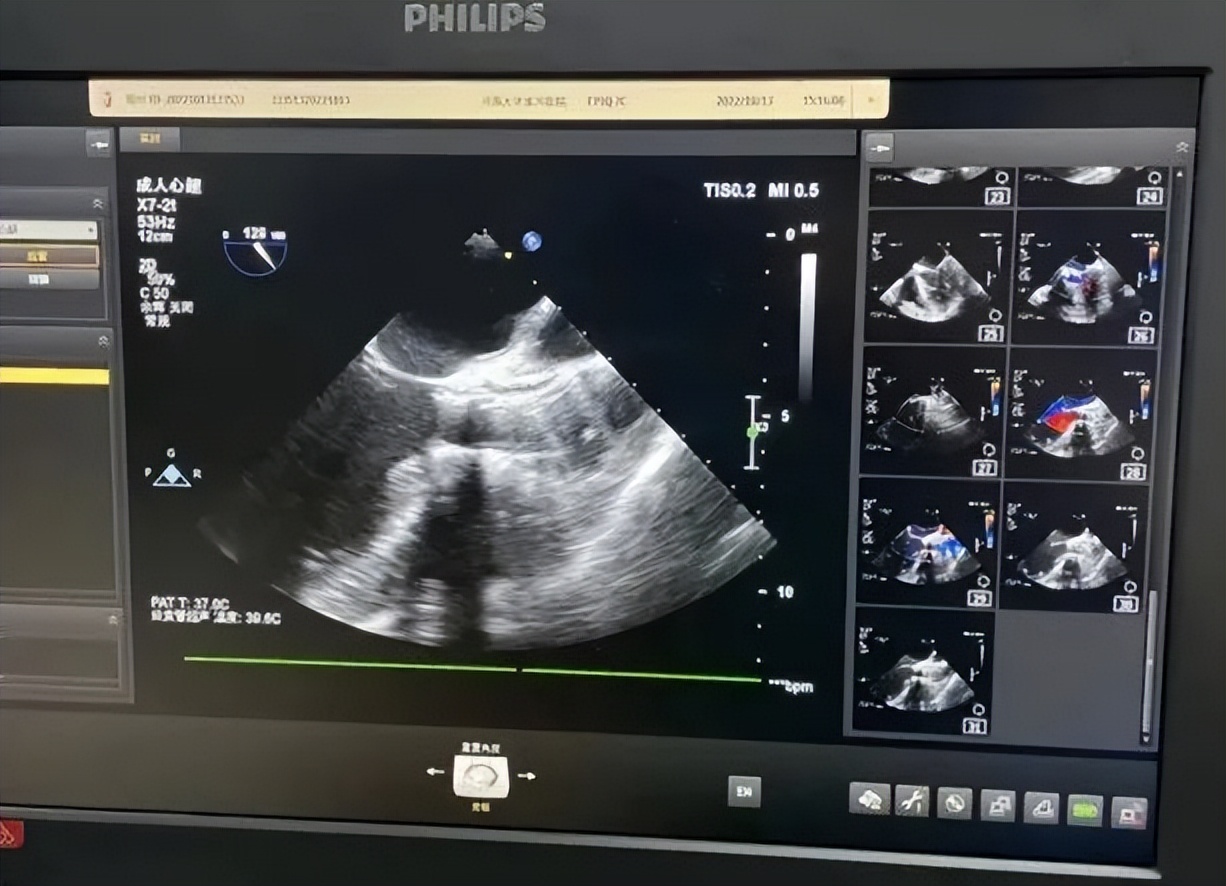

经过住院细致的临床观察与鉴别诊断,钟主任发现张爷爷存在二叶式主动脉瓣重度狭窄,主动脉瓣严重钙化,左室壁已经出现弥漫性增厚的情况,同时存在肺气肿、低氧血症、糖尿病。

▲心脏彩超资料